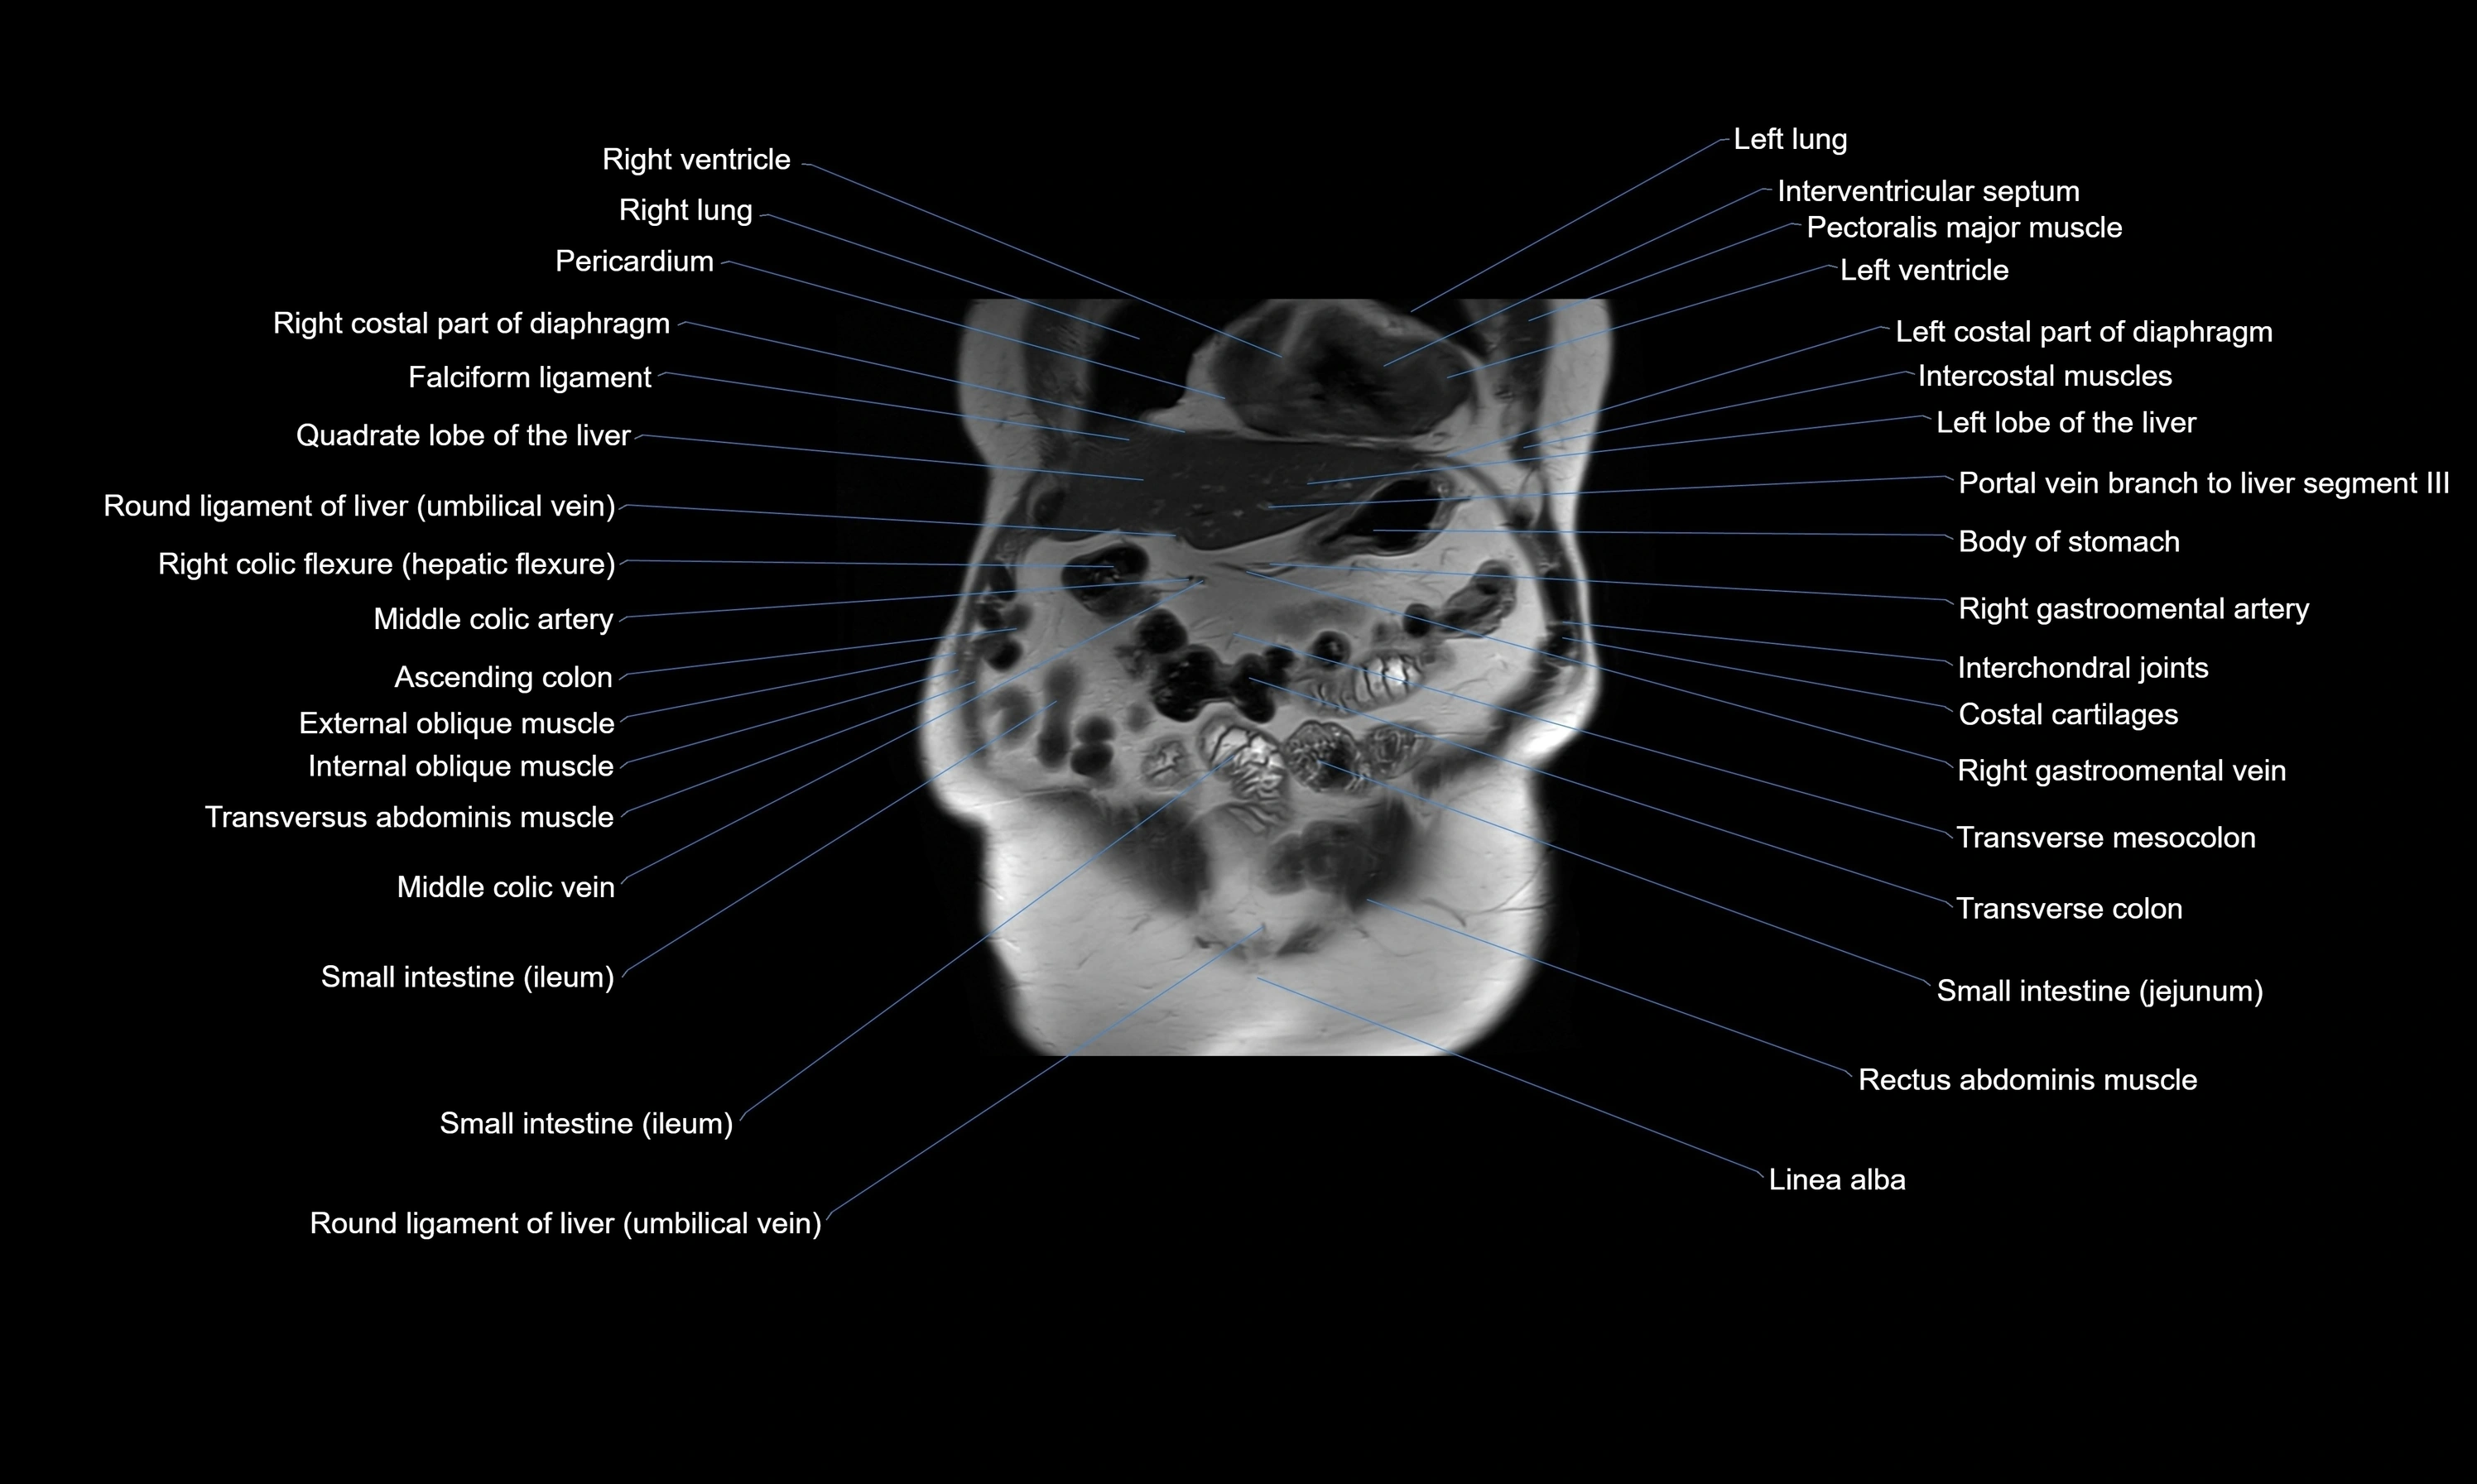

- Liver

- Stomach

- Transverse colon

- Small intestine

- Rectus abdominis muscle

- Linea alba